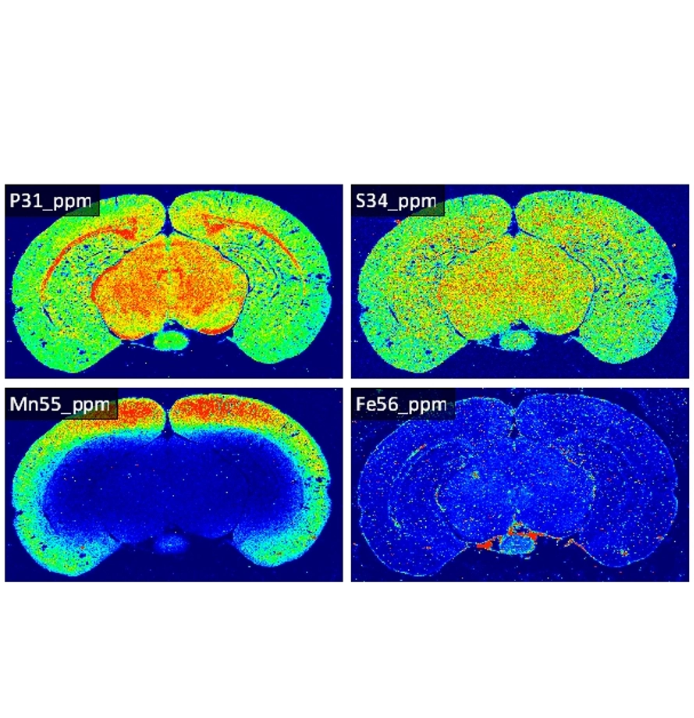

动物组织元素成像

5 方案描述